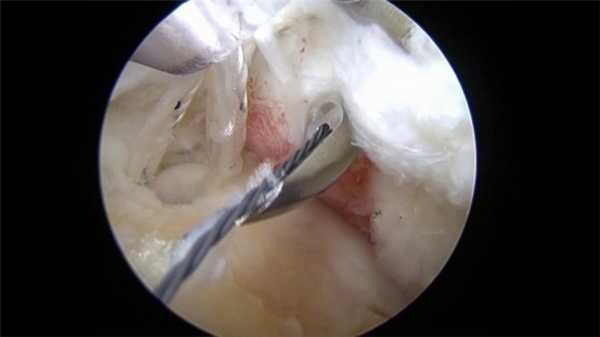

Обычно используется два/три прокола. В один вводится артроскоп, оснащенный источников света и микроскопической видеокамерой, которая передает изображение на монитор. Это позволяет подробно разглядеть все структуры. Одна или два других пункции используются для введения микрохирургических инструментов, необходимых для проведения операции.

Вид изнутри на сустав.